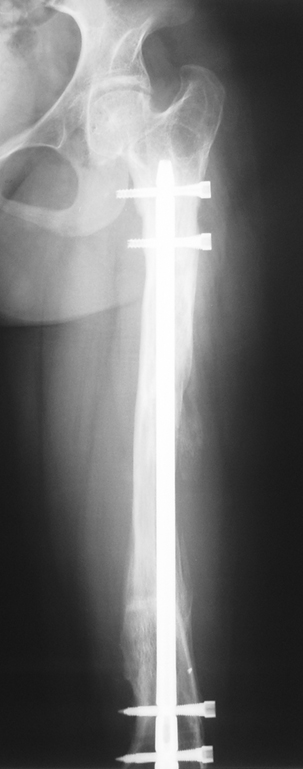

3. POSTTRAUMATIC LOWER LIMB SHORTNESS (MALUNION)

This type of shortness occurs after a fracture heals in a shortened position. Most cases are seen in adults and can be treated with one lengthening operation. Additional deformities can be corrected simultaneously. Most of these cases can be treated with lengthening over nail or just corrections and intramedullary nailing.